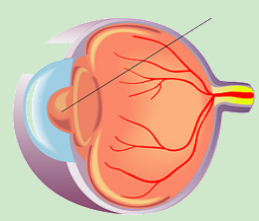

3.png

正常眼底造影